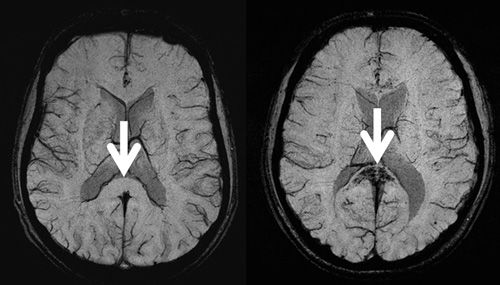

Use of functional MRI scans to detect leukoaraiosis benefits patients undergoing brain mapping for surgery or other treatments.